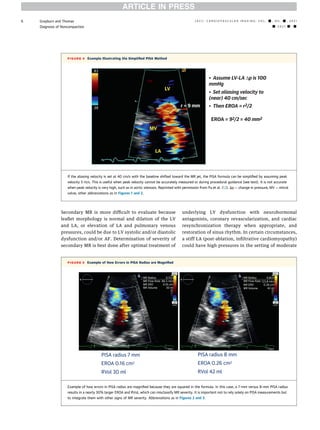

Proximal Isovelocity Hemispheric Radius from the Orifice. Obtain a CFD of the MR Jet with a good PISA formation under zoomed view. Web To calculate EROA for mitral valve effective regurgitant orifice area.

Web The Cardiac Catheterization Handbook 4th Edition. The radius is from the center of the PISA formation typically from the center of the valve to the first aliasing velocity. The calculators provided are not meant.

Measure the Diameter of the PISA radius. Web This mitral regurgitation PISA calculator determines the regurgitant volume effective regurgitant orifice and volume flow rate based on Doppler measurements. Calculation of orifice area in patients.